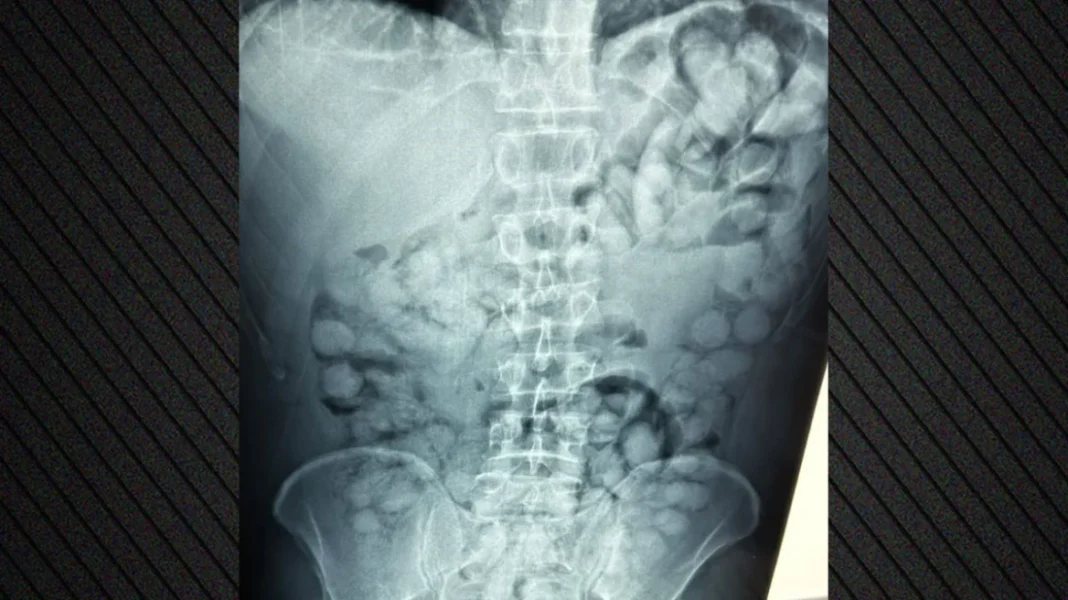

Ένας άνδρας, από τη Βραζιλία, συνελήφθη σήμερα το πρωί στο αεροδρόμιο «Ελ. Βενιζέλος», κατηγορούμενος ότι είχε καταπιεί σημαντική ποσότητα κοκαΐνης.

Σύμφωνα με την ΕΛΑΣ, ο άνδρας έφτασε στην Αθήνα, μέσω Παρισιού και στον έλεγχο που διενεργήθηκε, διαπιστώθηκε ότι είχε καταπιεί περίπου 100 συσκευασίες κοκαΐνης.